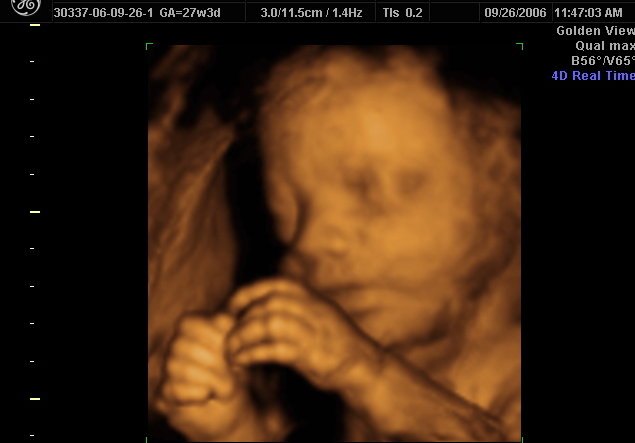

3d 4d Ultrasound Tulsa Ok

Image Gallery Little Bellies Oklahoma Pregnancy Spa

Sonogram Clinic 3d 4d Ultrasound Centers In Oklahoma Usa

Baby Blip 3d 4d Ultrasound Studio Offers Love At First Sight